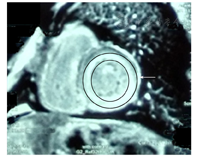

其中6例患者行心脏磁共振成像,均有不同程度的钆剂延迟强化,5例延迟强化以左心室壁心内膜下为主,1例延迟增强显示心肌壁内晕状强化(图2)。

心肌淀粉样变性的无创辅助检查应重点关注心电图、超声心电图及心脏磁共振成像。本研究中所有患者均有双房增大,均有不同程度的室间隔或左心室壁增厚,7例(87.5%)患者同时出现心电图肢体导联低电压和超声心动图示左心室壁增厚。研究显示心肌淀粉样变性心电图最具特征性的表现是电压普遍降低[5],典型超声心动图表现为在没有高血压的情况下左心室壁增厚,双房扩大,心肌回声增强,特别是颗粒样回声增强,大多数患者均有心室舒张功能障碍。结合心电图和超声心电图的特异性改变,将有助于提高心肌淀粉样变的诊断率,其诊断心肌淀粉样变性的敏感度为63%~80%[6]。心肌淀粉样变性患者心脏磁共振成像呈钆延迟显像,且形式多样,可局限或弥漫,见于心内膜下或跨心肌壁,约2/3心肌淀粉样变性患者可见整体心内膜下钆延迟显像。本研究中仅有6例患者行心脏磁共振成像检查,但均提示钆延迟显像,5例延迟强化以左心室壁心内膜下为主,提示较典型的心肌淀粉样变,1例延迟增强显示心肌壁内晕状强化,无特异性改变。有研究证实,对于心肌淀粉样变患者的诊断,心脏磁共振成像呈钆延迟显像与心内膜心肌活检具有较好的一致性[7]。